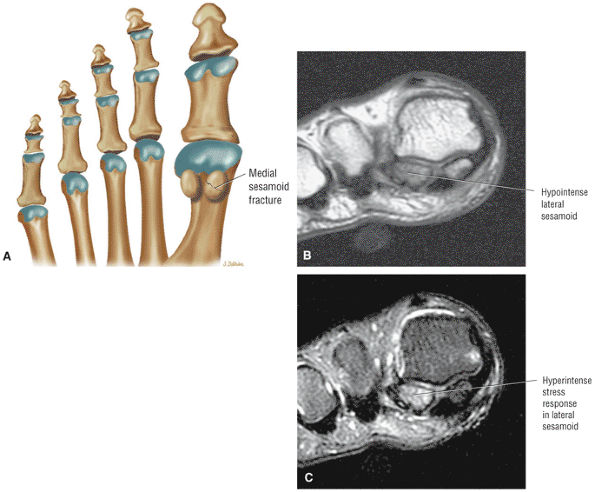

![]() |